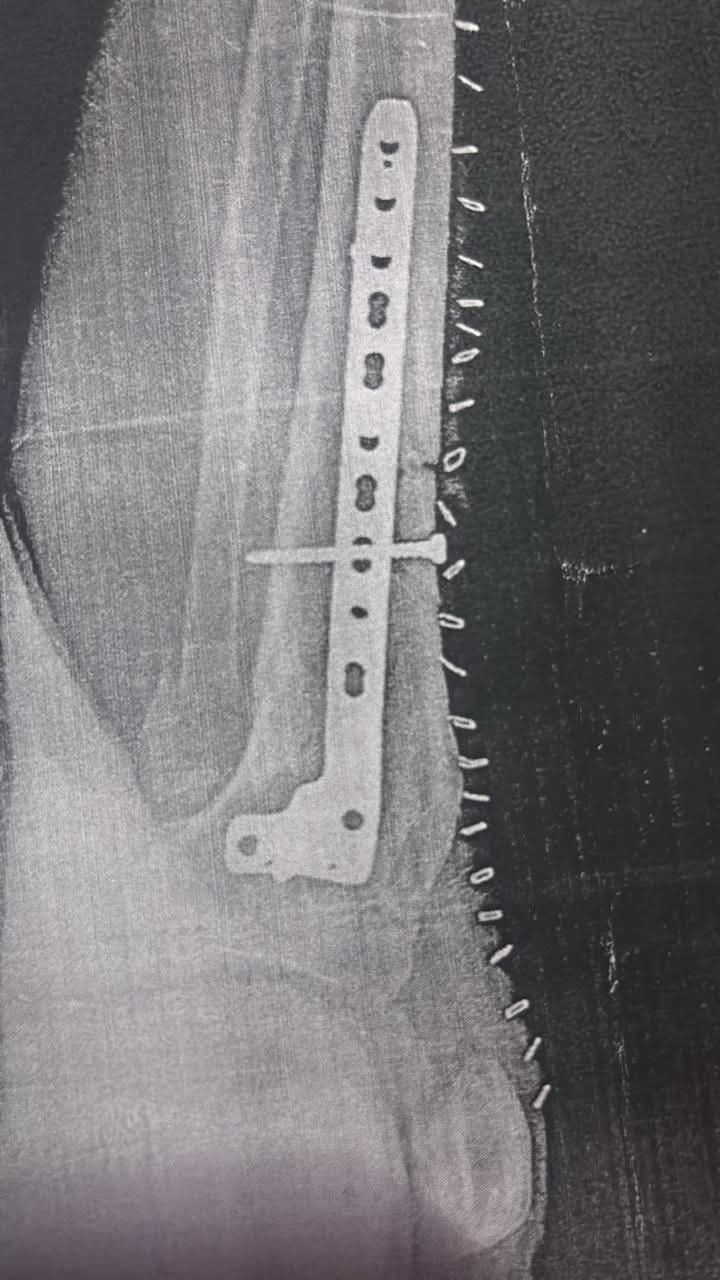

दुर्घटना में भगत गोण्डारे की एक टांग टूट गई, साथ ही शरीर के अन्य हिस्सों में भी गंभीर चोटें आई हैं। प्राथमिक उपचार के बाद उन्हें दीपका अस्पताल से जिला अस्पताल और फिर न्यू कोरबा हॉस्पिटल रेफर किया गया, जहां उनका ऑपरेशन किया गया। इलाज आयुष्मान कार्ड के माध्यम से कराया गया।

हादसे को डेढ़ महीना बीत जाने के बाद भी उनकी स्थिति पूरी तरह सामान्य नहीं हो पाई है। वर्तमान में उन्हें लगातार दवाइयों, फॉलो-अप इलाज और देखभाल की आवश्यकता है, जिसके चलते परिवार आर्थिक संकट से जूझ रहा है।